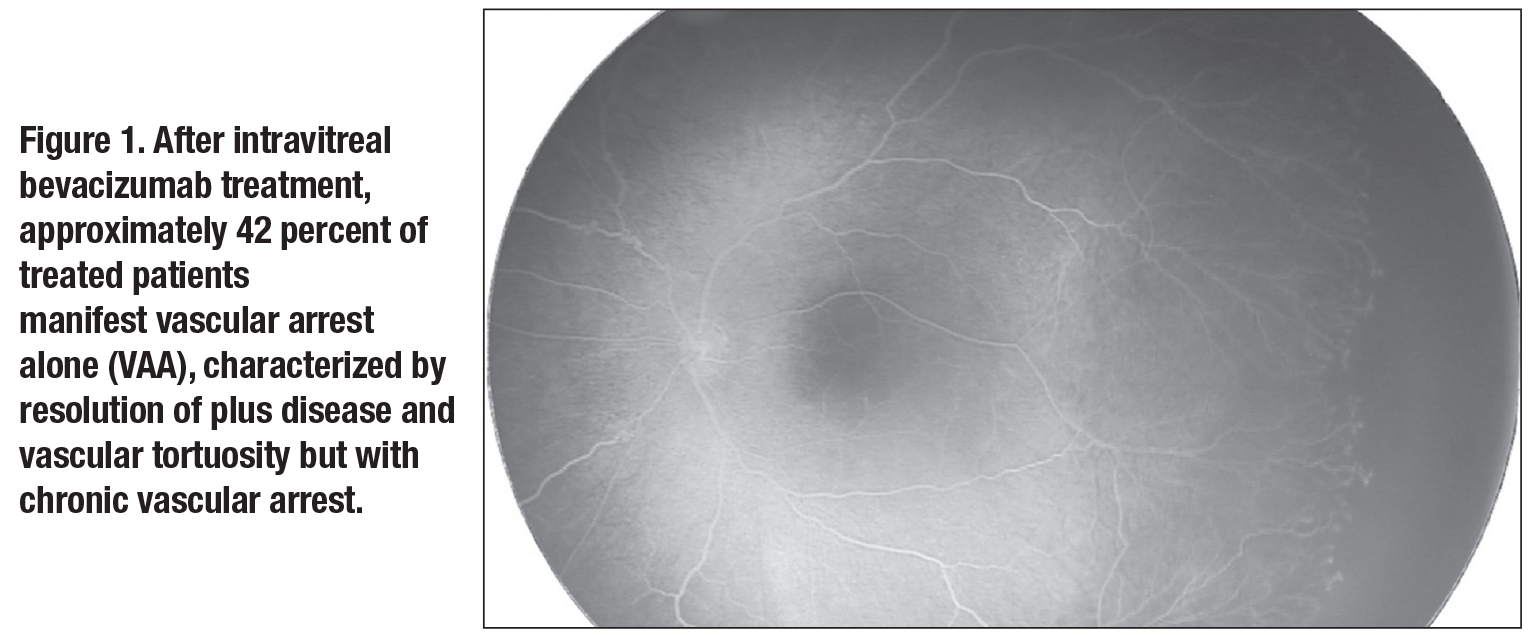

Of the eyes that did not completely vascularize (n=89), they found that 39 (43.8 percent) experienced resolution of plus disease and vascular tortuosity, but had chronic vascular arrest, termed “vascular arrest alone” (VAA, Figure 1, page 29). Thirty-four eyes (38.2 percent) didn’t experience resolution of vascular tortuosity while also displaying chronic vascular arrest, termed “vascular arrest with tortuosity” (VAT, Figure 2, page 30). Sixteen eyes (18 percent) had reactivated ROP, defined as recurrence of stage of disease; these were acutely treated with ablative laser.

Therefore, when considering all IVB treated eyes (n=92), approximately 3

percent reached full vascular maturation, 42 percent exhibited VAA, 38 percent exhibited VAT and 17 percent exhibited disease reactivation (Figure 3, page 33). This series reported no retinal progressive detachments. All patients not reaching full vascular maturation (97 percent) underwent ablative laser therapy at the time of FA (typically at around 60 weeks PMA).